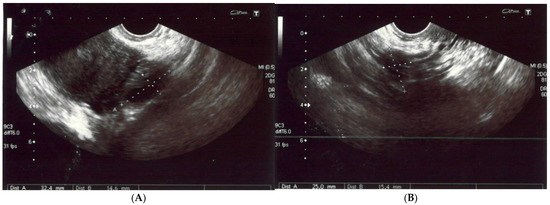

A 56-year-old non-obese, non-smoking female (gravida one, para one) presented with severe diffuse headaches lasting for 2 months, accompanied by retro-orbital pain. She had no history of uterine fibroids according to sonography (Figure 1) nor had she had hormonal treatment after menopause or a hysterectomy. There were no abnormalities found during physical and neurological examinations. There was no pathological resistance nor tumors in the subcutaneous tissue upon palpation. The basic laboratory tests were within the normal ranges. The patient’s anti-HIV tests were negative. She had no history of neoplasm nor recurrent infections and she did not use steroids. There were no medical conditions that indicated immunodeficiency.

Figure 1.

(A,B) The left and right ovaries, with their diameters. The right ovary measured 25 × 15 mm and the left ovary 24 × 14 mm. (C) The transverse plan of the uterus at its widest dimensions. In this plane, the uterine width (Ut-W) was measured. The uterus was of normal size in anterior flexion. (D) The midsagittal plane of the uterus showing the uterine fundus, myometrium, endometrium (6 mm thick), isthmus, cervix and cul-de-sac.